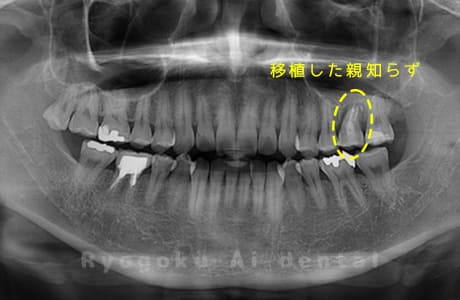

他院で右下の根の治療を行い、セラミックを被せる説明をされていたが、根の治療が終わらないため転院された患者さんです。隣の親知らずの抜歯の必要性と、根の治療を行なっている歯牙の予後が悪いため、移植治療を提案し、右下の親知らずの抜歯と同時に、右下の奥歯(7番)への移植治療を行いました。被せ物を行う必要もなく、順調に経過してます。